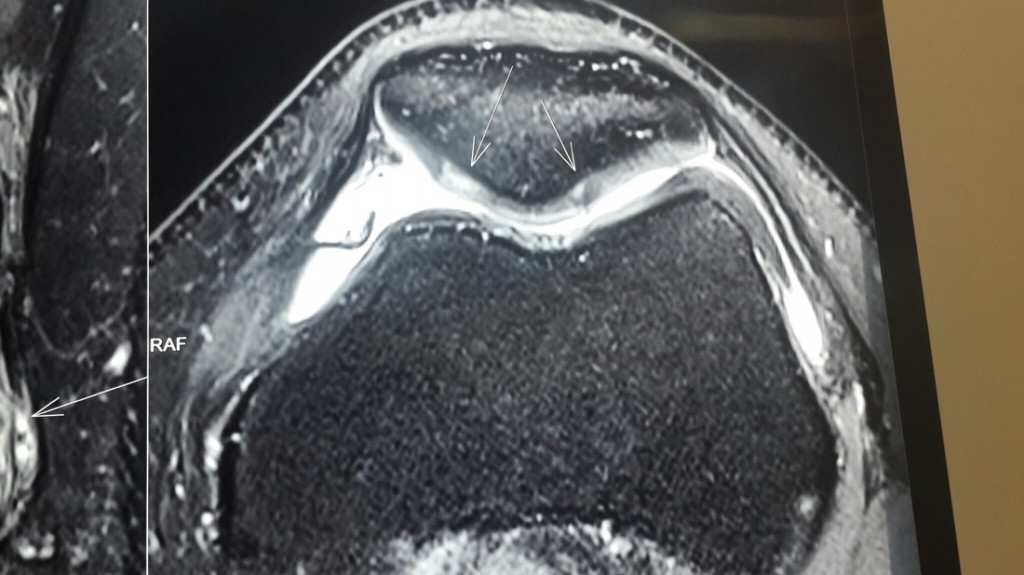

From ar.inspiredpencil.com

Mri Knee Cartilage Damage Knee Cartilage Loss Icd 10 What to do when you have no cartilage in your knee. Updated on november 28, 2023. m94.9 is a billable diagnosis code used to specify a medical diagnosis of disorder of cartilage, unspecified. articular cartilage defects of the knee comprise of a spectrum of disease entities from single, focal defects to advanced degenerative disease of articular. Get free. Knee Cartilage Loss Icd 10.

From www.researchgate.net

Clinical cases of the MR knee cartilage visualization, including the... Download Scientific Knee Cartilage Loss Icd 10 articular cartilage defects of the knee comprise of a spectrum of disease entities from single, focal defects to advanced degenerative disease of articular. Updated on november 28, 2023. What to do when you have no cartilage in your knee. icd 10 code for other articular cartilage disorders, unspecified site. By kristen gasnick, pt, dpt. Get free rules, notes,. Knee Cartilage Loss Icd 10.